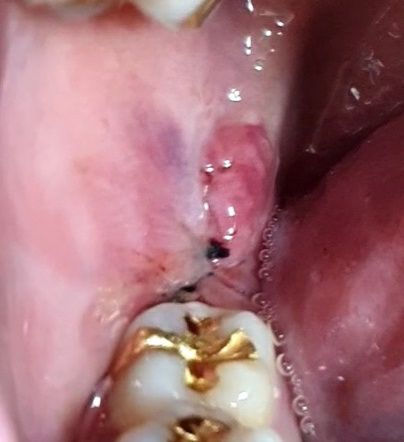

어제 사랑니 뽑았는데 실밥 빠진건가요? (사진 O)

1. 어제 사랑니 오른쪽 위 아래 뽑았는데 사진처럼 까맣게 뭔가 저렇게 튀어나와 있녜요 수프나 죽 밖에 안먹고 양치질도 저기로 절대 안했는데.. 문제 있는 건가요?

2. 3번째 사진에서 빨간색 동그라미로 표시했는데 알갱이 같은 저건 뭘까요? 저긴 사랑니 부위가 아닌것 같은데 갑자기 생겨났네요 ;;

1. 말씀하신 부위는 실밥입니다. 아직까지 발치 이후 연조직이 충분히 회복되지 않아 실밥의 위치가 제대로 잡혀 보이지 않아 보입니다. 큰 문제는 없습니다.

2. 사랑니 발치 전에 잇몸을 절개하게 되며 잇몸 절개 이후에 아직까지 회복되지 않은 연조직입니다.

-까맣게 튀어 나온게 실밥입니다.

-사랑니 발치시 잇몸이 부어서 일시적으로 잇몸이 밀려서 그러는거니 크게 걱정하지 않으셔도 됩니다.

아직 부기가 있어보이나 실밥이 빠진것같지 않습니다..잇몸절개 부위는 치유되는 과정이니 염려 안해도 괜찮을것 같습니다.